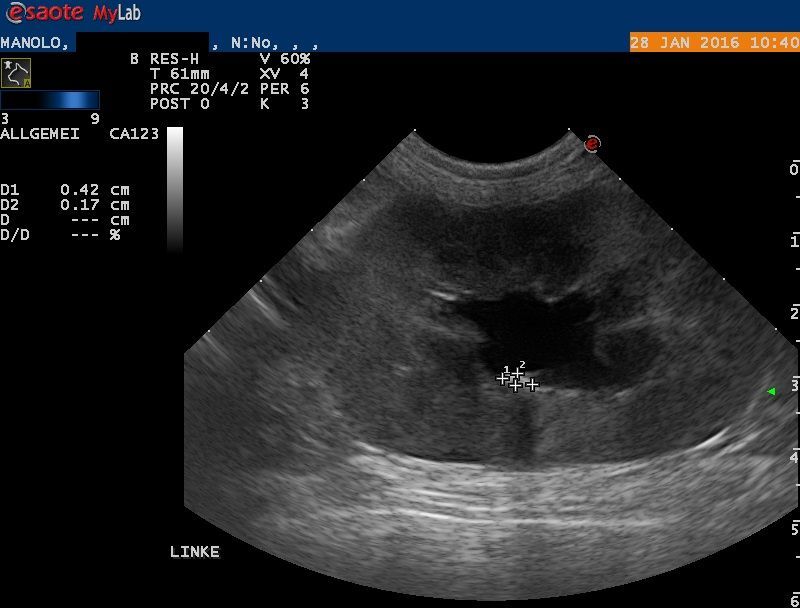

Der Bauch von Manolo wird mittels Ultraschall untersucht: Die rechte Niere erscheint klein und weist eine veränderte Architektur auf. Die linke Niere ist deutlich vergrössert; das Nierenbecken ist erweitert, und auch der ableitende Harnleiter ist deutlich erweitert. Im Nierenbecken findet sich ein kleiner Nierenstein von ca 4x2x2 mm Grösse. Mittels steriler Punktion wird Urin aus der Harnblase entnommen - im Urin befinden sich grosse Mengen rote und weisse Blutkörperchen sowie Baktieren, auch ist der Harn wenig konzentriert.

Weiterer Verlauf: 2 Monate später

Das eingesetzte System sollte alle 3 Monate gespült werden, um das einwandfreie Funktionieren zu gewährleisten. Beim Besuch am Tierspital 2 Monate nach der Operation geht es Manolo sehr gut, die Nierenwerte sind beinahe normal, und die Spülung des SUB ist dank der Kooperation der Katze sogar ohne Narkose möglich. Der Urin enthält keine Bakterien mehr.